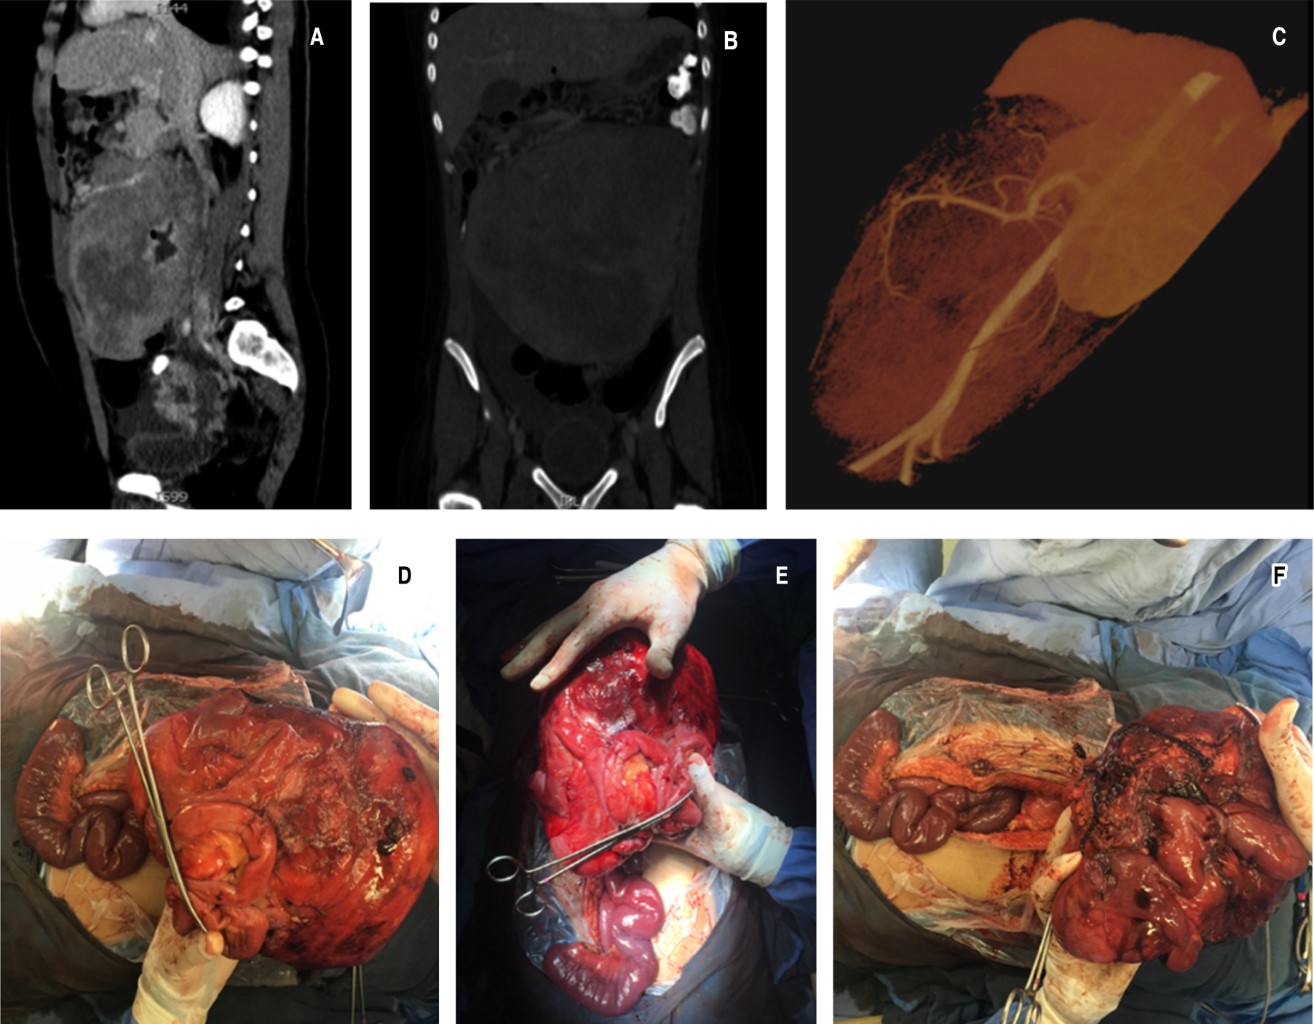

El diagnóstico por histopatología, a partir de la biopsia, fue de tumor retroperitoneal fibromatoso profundo. En un estudio por angiotomografía (Figura 1A-C) se corrobora masa tumoral dependiente de retroperitoneo que desplazaba la aorta y la vena cava inferior, con afección de toda la raíz del mesenterio rodeando la arteria mesentérica superior. Por el gran compromiso vascular y alto riesgo de mortalidad se decide no resecar la tumoración, y solamente se administró quimioterapia a base de vincristina, etopósido y carboplatino, egresando a domicilio.

Tres días después, acudió a urgencias con datos de obstrucción intestinal por lo que se realiza segunda laparotomía, con resección de la tumoración, a pesar del mal pronóstico. Se encontró tumoración de 30 × 25 cm, fija, muy vascularizada y cruenta, efectuando resección intestinal en bloque (Figura 1D-F). Tras un mes del reingreso, se realiza una tercera laparotomía para evaluar viabilidad de asas intestinales ante compromiso de la arteria mesentérica; sin embargo, se detectó necrosis de yeyuno, íleon y colon ascendente, por lo que se realiza resección intestinal total y gastrostomía. Al tercer día de esta cirugía, se inició NPT, la cual se suspendió a los 14 días por cuarta laparotomía debido a datos de complicaciones intraabdominales. Posteriormente se colocó catéter permanente venoso central para reiniciar NPT, pero se suspendió aproximadamente dos meses después por colonización del catéter. Tras 25 días de rescate de catéter, nuevamente se comienza NPT, iniciando capacitación para que sea administrada en su domicilio.